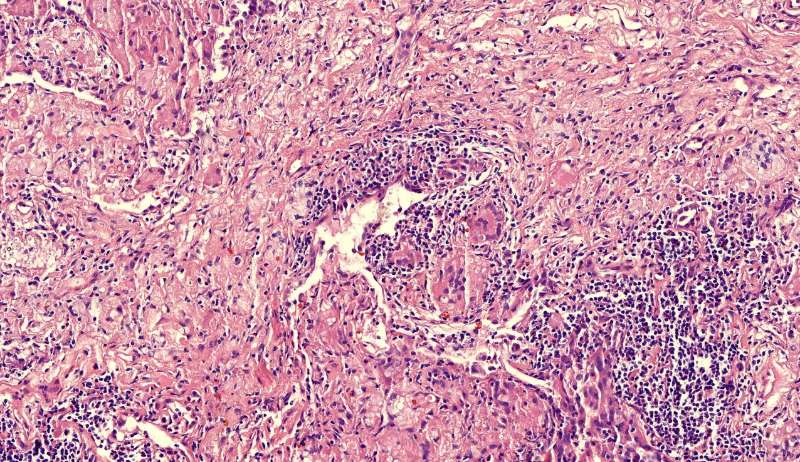

中性粒细胞很多,此处组织结构破坏

左侧液化,脓肿壁较规则平滑

周围的炎症机化区

破坏力在这里逐渐减弱

逐渐从中性粒细胞转为淋巴细胞为主